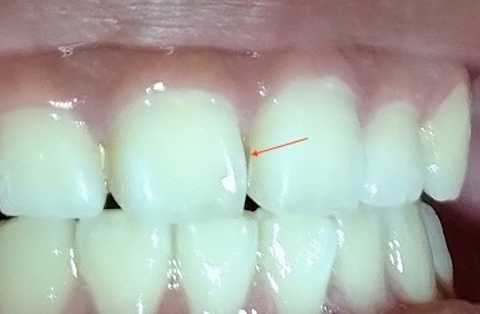

上顎のBefore/after

前歯の虫歯のBefore/after はこれだが、虫歯と言っても極表層だけで、そこにFeSが付着しているだけだと思う。飲食後の重曹うがいだけで維持管理できるのではないか?と思われる。

黒いFeSは歯を守ってくれていると考えるべきで、除去すると虫歯が進行する可能性が高い。